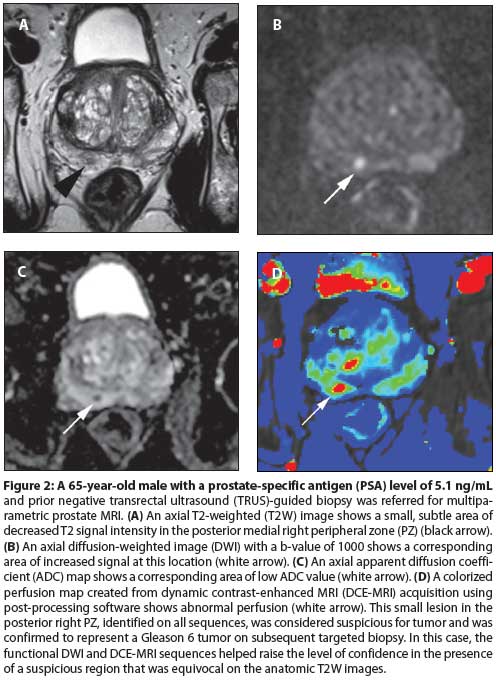

Multiparametric MRI is a promising tool for identifying cancer within the prostate. It has the potential to drastically change the way prostate cancer is staged and treated. However, work remains to make this technique reproducible and accessible to the community-based radiologist and urologist.